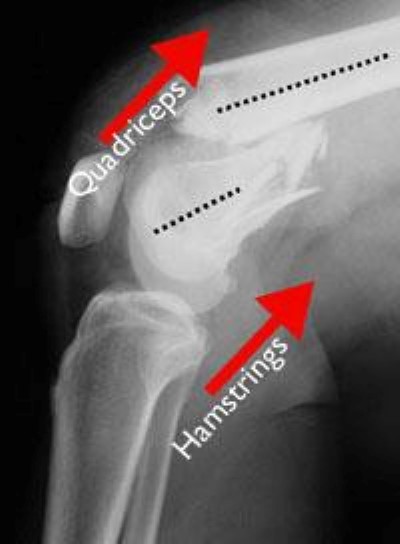

When the distal femur breaks, both the hamstrings and quadriceps muscles tend to contract and shorten. When this happens the bone fragments change position and become difficult to line up with a cast.

Distal femur fracture in which the bones are out of alignment

In this X-ray of the knee taken from the side, the muscles at the front and back of the thigh have shortened and pulled the broken pieces of bone out of alignment.